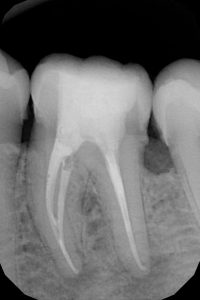

TREATMENTS

SERVICES

| 19 | Root Canal Treatment Conventional |

| 20 | Rotary RCT |

| 21 | Root Canal Treatment With Thermafil |

| 22 | Root Canal Treatment With Obtura (II) |

| 23 | Root Canal Treatment With Calamus |

| 24 | Regenerative Endodontics |

| 25 | Surgical Endodontics (Microscope) |